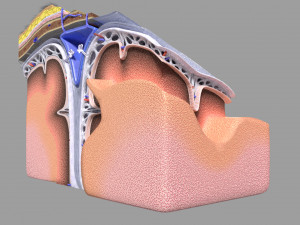

A blend model of brain along with its covering layers (meninges), skull bone and scalp labelled in detail and anatomically precise. The parts depicted are white, gray, pia, arachnoid, dura, bone, skin, fat, aponeurosis, periosteum, falx cerebri and more.

The material is high resolution image textures and normal maps based on non overlapping UVs. The texture and normal maps are packed with the blend file itself.